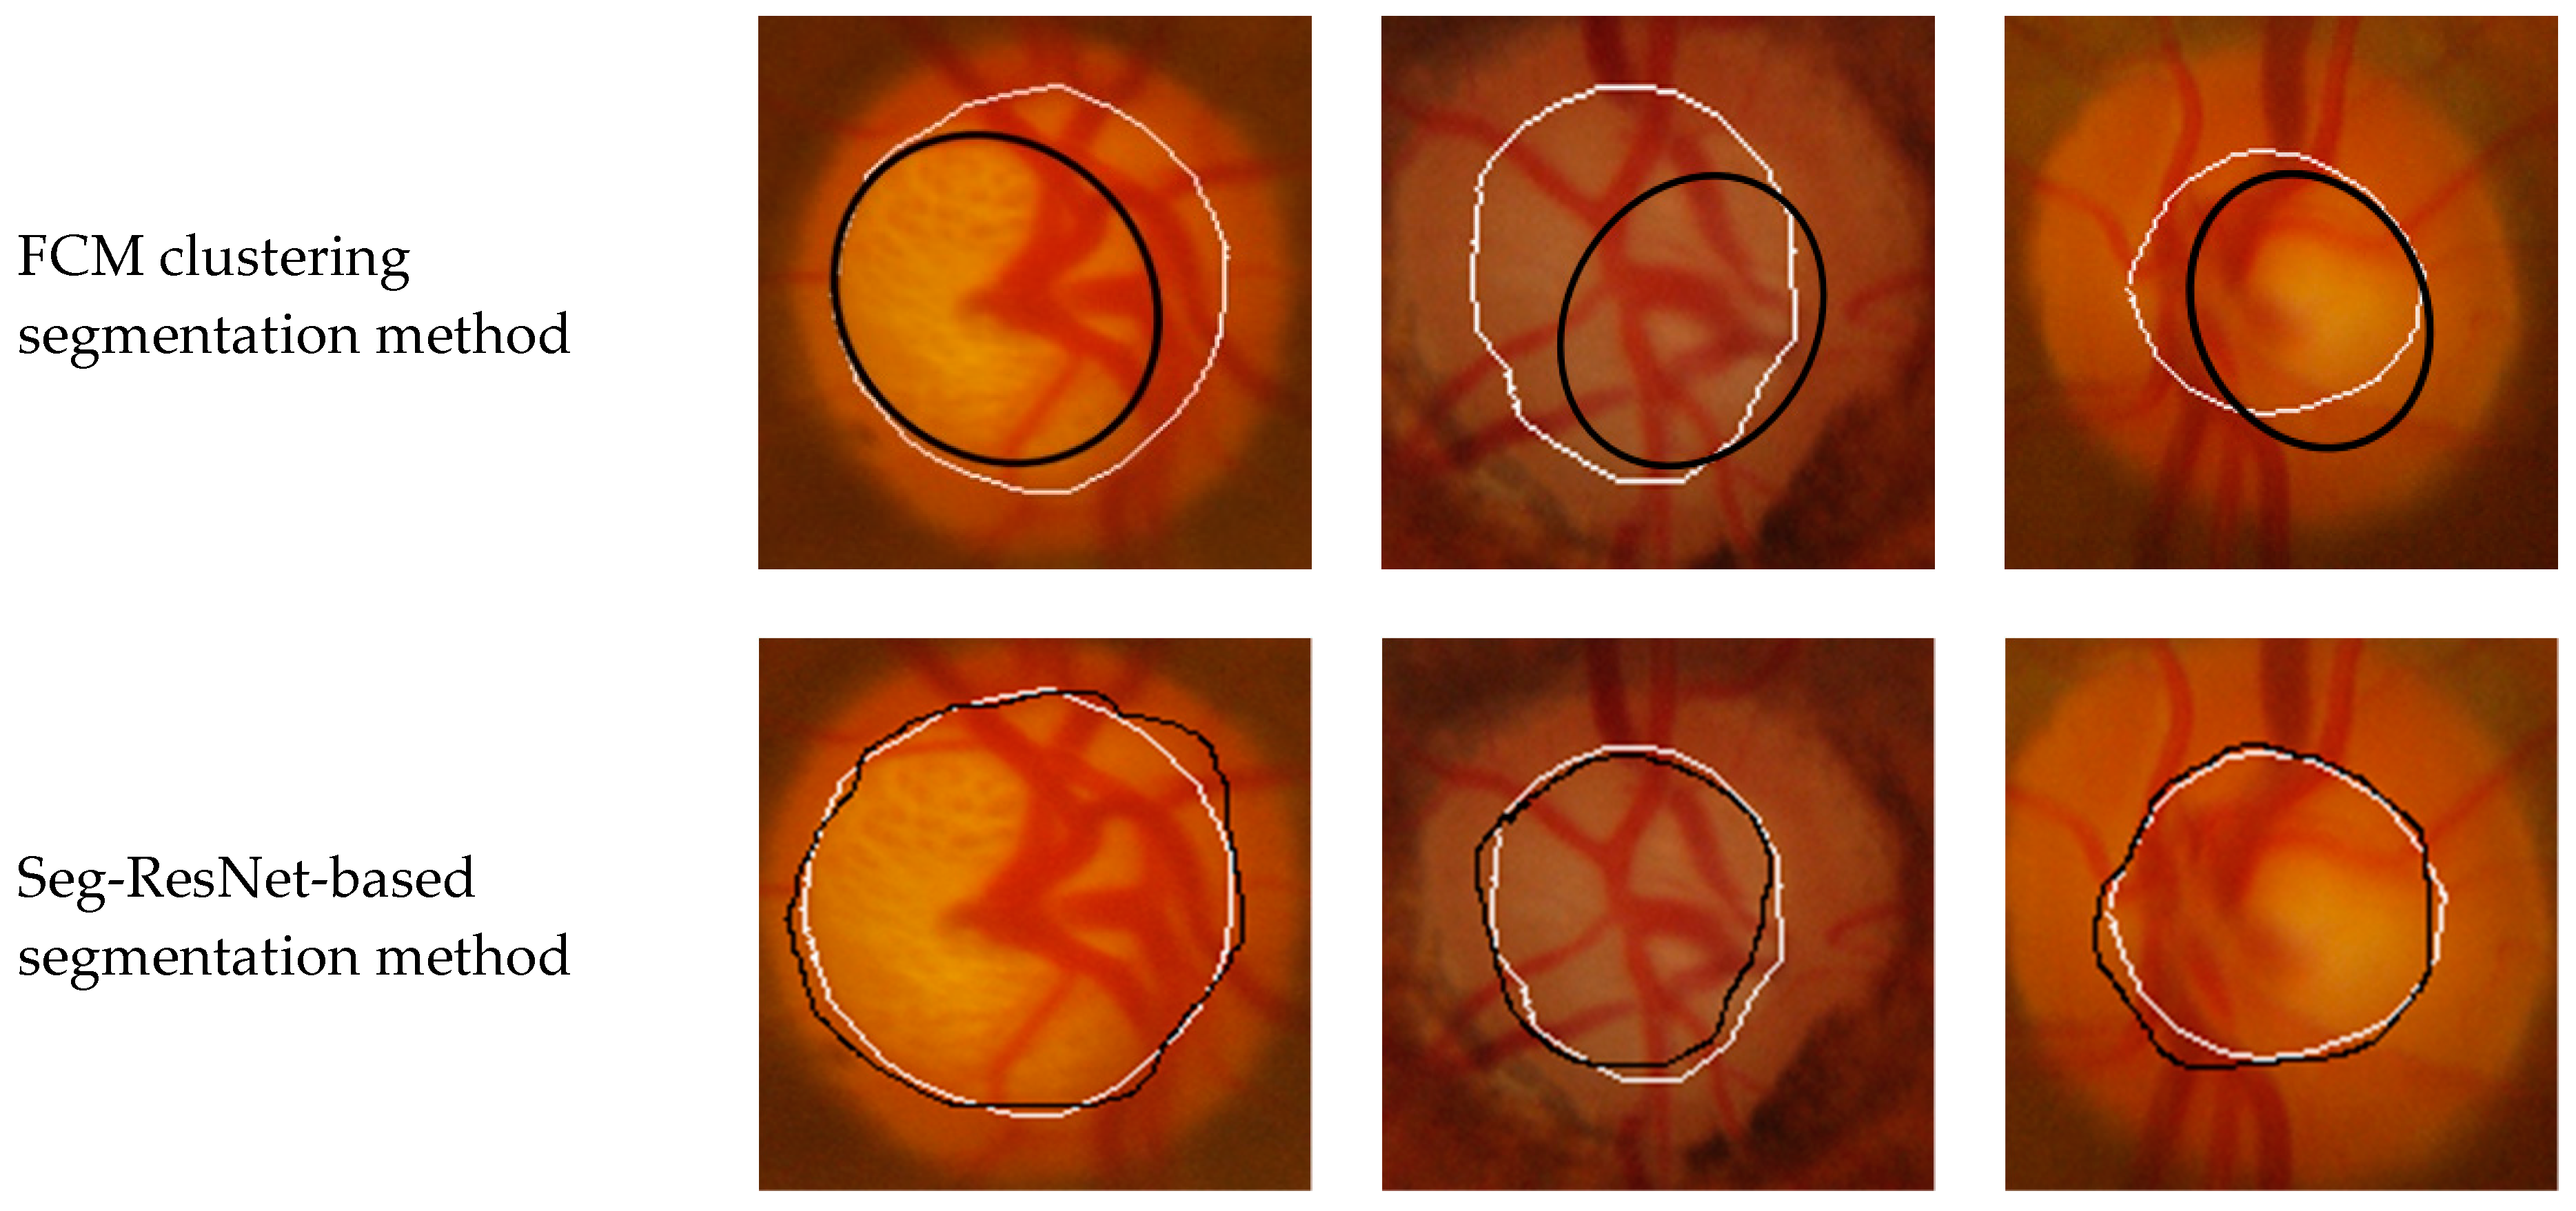

To verify the performance of the Seg-ResNet network-based optic cup segmentation method proposed in this paper, we compared our method to the FCM cluster segmentation method. The segmentation results are shown in Figure 9 and Figure 10.

• GlaucomaRepo database segmentation results.

• Drishti-GS database segmentation results.

The optic cup segmentation method, based on FCM clustering, fully considered the brightness information of the image and the characteristics of the blood vessel bending point falling on the edge of the optic cup. However, due to the complicated fundus image, the extraction of the optic cup needed to undergo a series of preprocessing steps, including disc segmentation, region of interest extraction, blood vessel extraction, blood vessel bending point detection, optic cup rough segmentation, and ellipse fitting. Each step was sequential, i.e., each operation was based on the previous operation. If the result of an operation was inaccurate, then it would have had a greater impact on the final result. The division of the optic cup by conventional methods would inevitably be compounded by each pre-processing operation. Figure 9 and Figure 10 show that the conventional method could not accurately divide the optic cup in cases of low cup plate contrast and severe vascular occlusion, while the segmentation effect on the Drishti-GS data set was poor. The results were likely affected by the fact that the GlaucomaRepo data set and the Drishti-GS data set were taken from different fundus cameras, thus the imaging quality varied greatly. The overall gray value of the Drishti-GS data set was low, the vascular occlusion was severe in most images, the method used for filling the neighborhood pixels was not obvious, the FCM optic cup clustering was affected by vascular interference, and the segmentation effect was below average. Traditional image processing techniques are difficult to change between these two data sets, so traditional image processing technology is less robust than the optic cup segmentation method. The depth-based learning method based on deep learning methods used a large number of data sets, where each image was taken from different cameras in different shooting environments. Thus, the feature extraction method had strong adaptability and also showed excellent segmentation effects in different test sets. Figure 9 and Figure 10 show optic cup segmentation using a depth-based learning method, which not only learned the brightness characteristics of the optic cup, but also learned the characteristics of blood vessel bending at the edge of the optic cup. This was seen in both the GlaucomaRepo data set and the Drishti-GS data set; this information could be used to accurately divide the optic cup. Table 3 and Table 4 compare the segmentation performance of the deep learning methods using two different traditional databases. Overall, optic cup segmentation based on depth-based learning methods had higher precision and robustness over the traditional image processing technology.

Figure 10. Comparison of segmentation results of Drishti-GS database based on the Seg-ResNet method and the FCM clustering optic cup segmentation method.

Symmetry 11 00933 g010